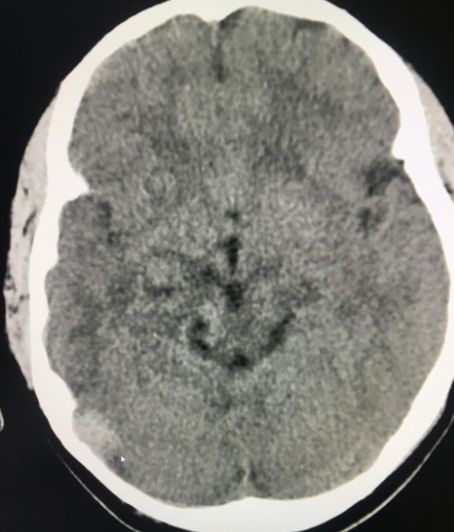

全新日本进口佳能金刚螺旋CT

该新设备功能先进,有平扫、三维重建、X线计算机体层成像等功能,能对人的头部、颈部、胸腔、四肢、盆腔等多个部位进行扫描成像。

现在医院引进了全新的进口螺旋CT,患者直接就能在医院确诊,节约了患者的时间,并且,进口的螺旋CT机扫描图像质量好,显示清晰。

硬膜外血肿

该设备自运行以来,发现并确诊不少疾病:颈椎椎间盘突出、 腰椎椎间盘膨出伴双侧神经根受压、硬膜外血肿、右侧上颌窦炎、右侧筛窦炎、双肺感染伴双侧胸腔积液、心包积液、右侧胸腔包裹性积液、原发性肝癌伴骨转移等疾病。